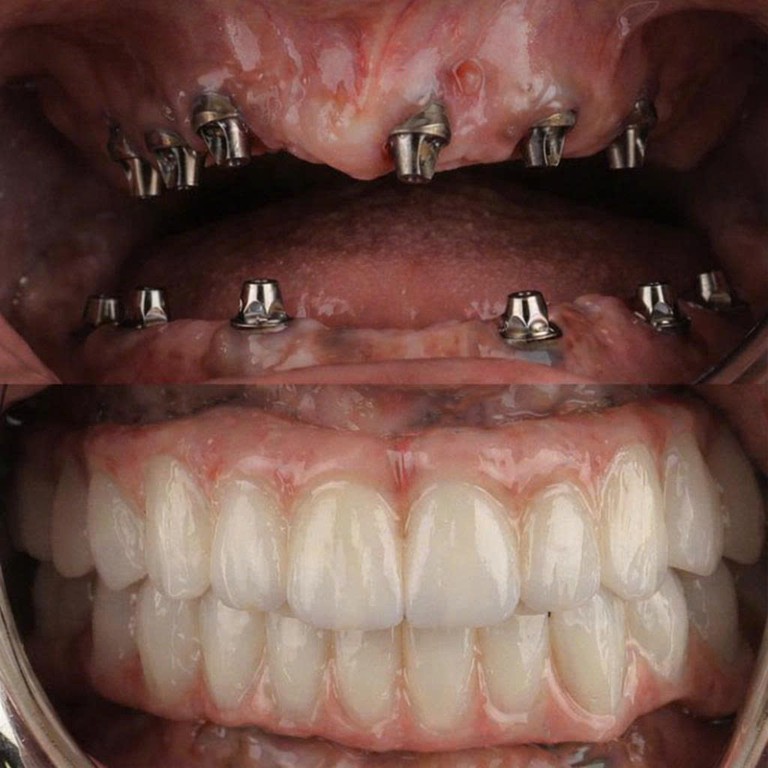

Cấu Tạo Của Một Chiếc Răng Implant

Răng Implant có cấu trúc gồm 3 phần chính, mô phỏng gần giống cấu tạo răng thật – giúp phục hồi cả chức năng ăn nhai lẫn thẩm mỹ.

Trụ Implant (Titanium)

Được cấy trực tiếp vào xương hàm, thay thế chân răng thật. Làm từ Titanium – vật liệu tương thích sinh học, tích hợp xương tự nhiên trong 3–6 tháng.

Khớp Nối Abutment

Là bộ phận kết nối giữa trụ Implant và mão sứ. Abutment truyền tải lực nhai từ mão sứ xuống trụ, đảm bảo độ vững chắc và ổn định lâu dài.

Mão Răng Sứ

Phần thân răng giả phía trên, được chế tác từ sứ cao cấp, hài hòa về màu sắc và hình dáng với răng thật. Tuổi thọ 15–20 năm, có thể thay mới dễ dàng.

Mất Răng Toàn Hàm

- Ăn nhai khỏe như thật

- Ngăn tiêu xương, giữ nét

- Tự tin cười, giao tiếp

Khám & Chụp CT 3D

Bác sĩ khám tổng quát, chụp phim Cone Beam CT 3D, lập kế hoạch điều trị chi tiết.

Cấy Trụ Implant

Gây tê vùng, đặt trụ chính xác bằng máng hướng dẫn phẫu thuật. Chỉ 20–30 phút.